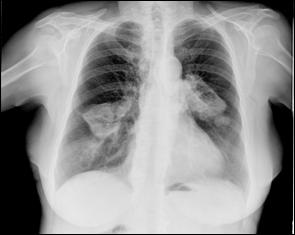

Cele mai multe metasteze la distanta, provocate de tumorile vezicale maligne, sunt localizate in plamani si in oase. Diagnosticul acestora se face prin: radiografii toraco-pulmonare, radiografii osoase sau scintigrame osoase (evidentiaza metastazele osoase cu 9-12 luni mai devreme decat expresia evidenta a acestora pe radiografiile standard).

dreapta Figura 45. Metastaze pulmonare multiple dintr-un carcinom vezical

infiltrativ.

Figura 4 Radiografie toraco-pulmonara cu metastaze pulmonare multiple

dintr-un carcinom vezical infiltrativ

Figura 47. Radiografie toraco-pulmonara cu metastaze pulmonare multiple dintr-un carcinom vezical infiltrativ.